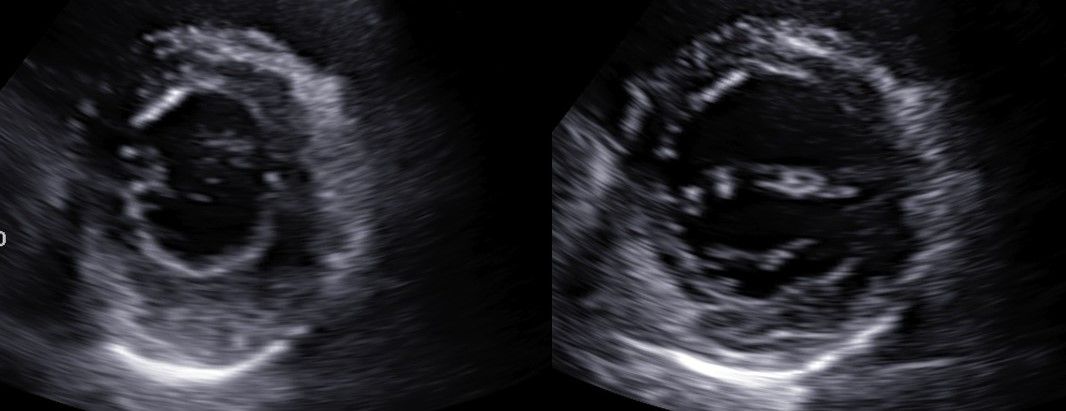

김포내과 삼성탑내과 심장초음파 검사안내심장초음파(Echocardiography)는 심장의 구조와 기능을 평가하기 위해 사용하는 비침습적 검사입니다. ✅ 검사방법: 초음파 푸르브(PROBE)에 젤리를 묻혀 검사를 진행합니다.✅소요시간: 경우에 따라 다를수 있지만 일반적으로 10분~30분 가량 소요 됩니다.✅통증 유무: 비 침슴적인 검사이므로 통증은 전혀 없습니다 **심장초음파의 주요 적응증(적응 대상)**✅ 1. 심잡음(Murmur)심잡음의 원인 감별 (판막 질환 여부 확인)✅ 2. 심부전 증상 평가호흡곤란, 하지 부종, 피로 등 → 심장의 수축 및 이완 기능 평가✅ 3. 심근경색 및 협심증심근의 운동 이상 여부, 좌심실 기능 평가✅ 4. 고혈압 환자의 심장 상태 평가좌심실 비대(hypertrophy), 이완기 기능 장애 여부 등 확인✅ 5. 판막 질환 의심 시승모판막협착증, 대동맥판막역류증 등 → 정확한 진단 및 중증도 평가✅ 6. 선천성 심질환심방 중격 결손(ASD), 심실 중격 결손(VSD) 등 진단✅ 7. 심낭 질환심낭삼출(pericardial effusion), 심장압전(cardiac tamponade) 여부 확인✅ 8. 심장종양 또는 혈전 의심 시심장 내 종물(mass), 혈전(thrombus) 감별✅ 9. 심인성 실신 평가구조적 심질환 여부 확인✅ 10. 심장 감염 질환감염성 심내막염(endocarditis) 의심 시 판막 위 식물(vegetation) 확인✅ 11. 심방세동(AF) 등 부정맥 평가기저 심질환(좌심방 확장, 판막 질환 등) 유무 확인✅ 12. 항응고 치료 전 심장 혈전 확인전기적 심율동전환(cardioversion) 전 좌심방 혈전 유무 평가 (특히 TEE 이용)필요 시에는 경흉부 심초음파(Transthoracic Echo, TTE) 외에도경식도 심초음파(Transesophageal Echo, TEE) 또는 운동부하 심초음파 등을 추가로 시행할 수 있습니다.✅ 삼성탑내과는 심초음파 경력 25년 으로 현재 대한 임상초음파학회 학술이사(심장)를 역임하고 있으며 대한 심초음파학회의 심초음파 인증의 자격을 보유하고 있습니다.